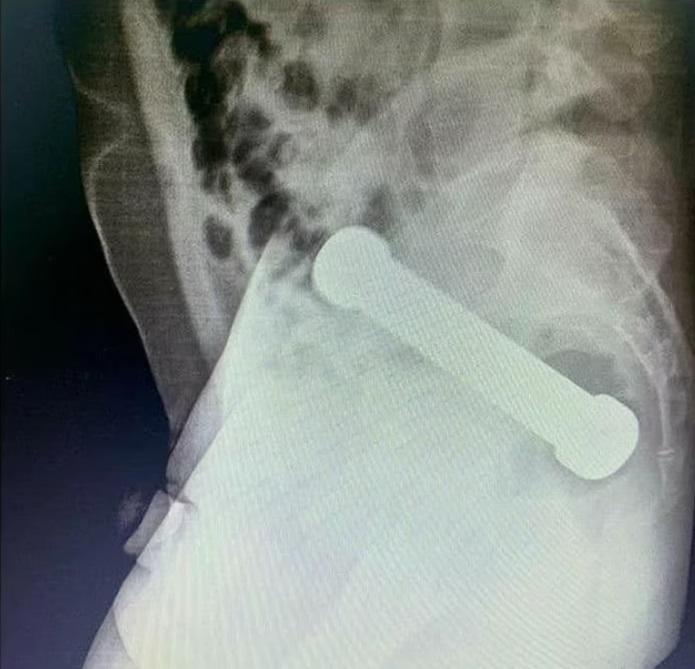

X光檢查顯示,啞鈴卡在男子的腸臟。(互聯網)

英國《每日郵報》報道,該名54歲男子把一個重2公斤、長20厘米的啞鈴塞進肛門後,發現無法取出,待了兩天後到Manaus一間醫院求醫,說腹痛、噁心、不能排便。報道指,醫生說該名男子在檢查時不合作,經X光檢查後發現,一個20厘米長的啞鈴卡在結腸與直腸連接的位置。

X光檢查顯示啞鈴的位置。(互聯網)